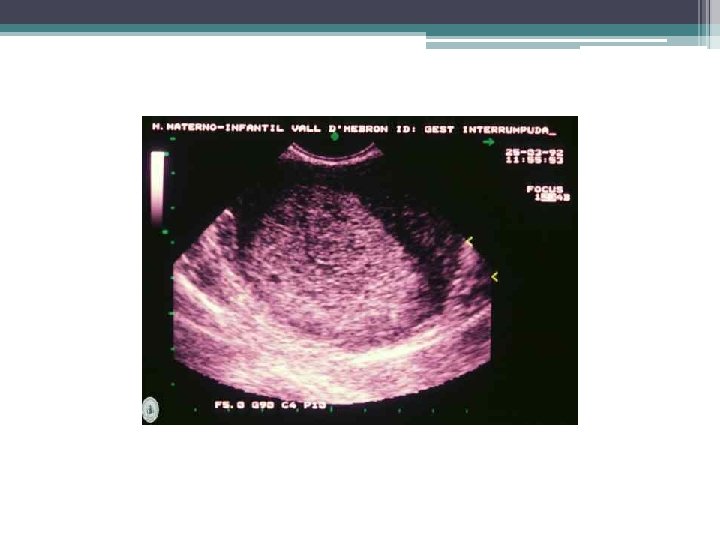

Aborto diferido o retenido Muerte del huevo in utero sin contracciones o sin dilatación suficiente del cuello uterino para la expulsión del mismo. • Ecografía: Ø Huevo muerto: regresión de las estructuras. ▫ Aborto reciente: Imágenes similar a un embarazo normal, pero sin actividad cardiaca y movimientos activos. ▫ Muerte + de 24 horas: alteraciones estructurales del embrión y del saco gestacional. Ø Huevo anembrionado: aumento inusitado sólo del saco ovular.